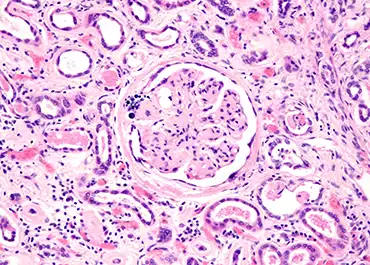

Diabetic Kidney Disease Detection

Analysis of urine Raman spectra differences from patients with diabetes mellitus and renal pathologies,” has been accepted for publication in the prestigious on-line journal, Peer J. This paper details the analysis of more than 250 urine specimens from Armed Services Veterans with our Rametrix® technology. An important finding from the...